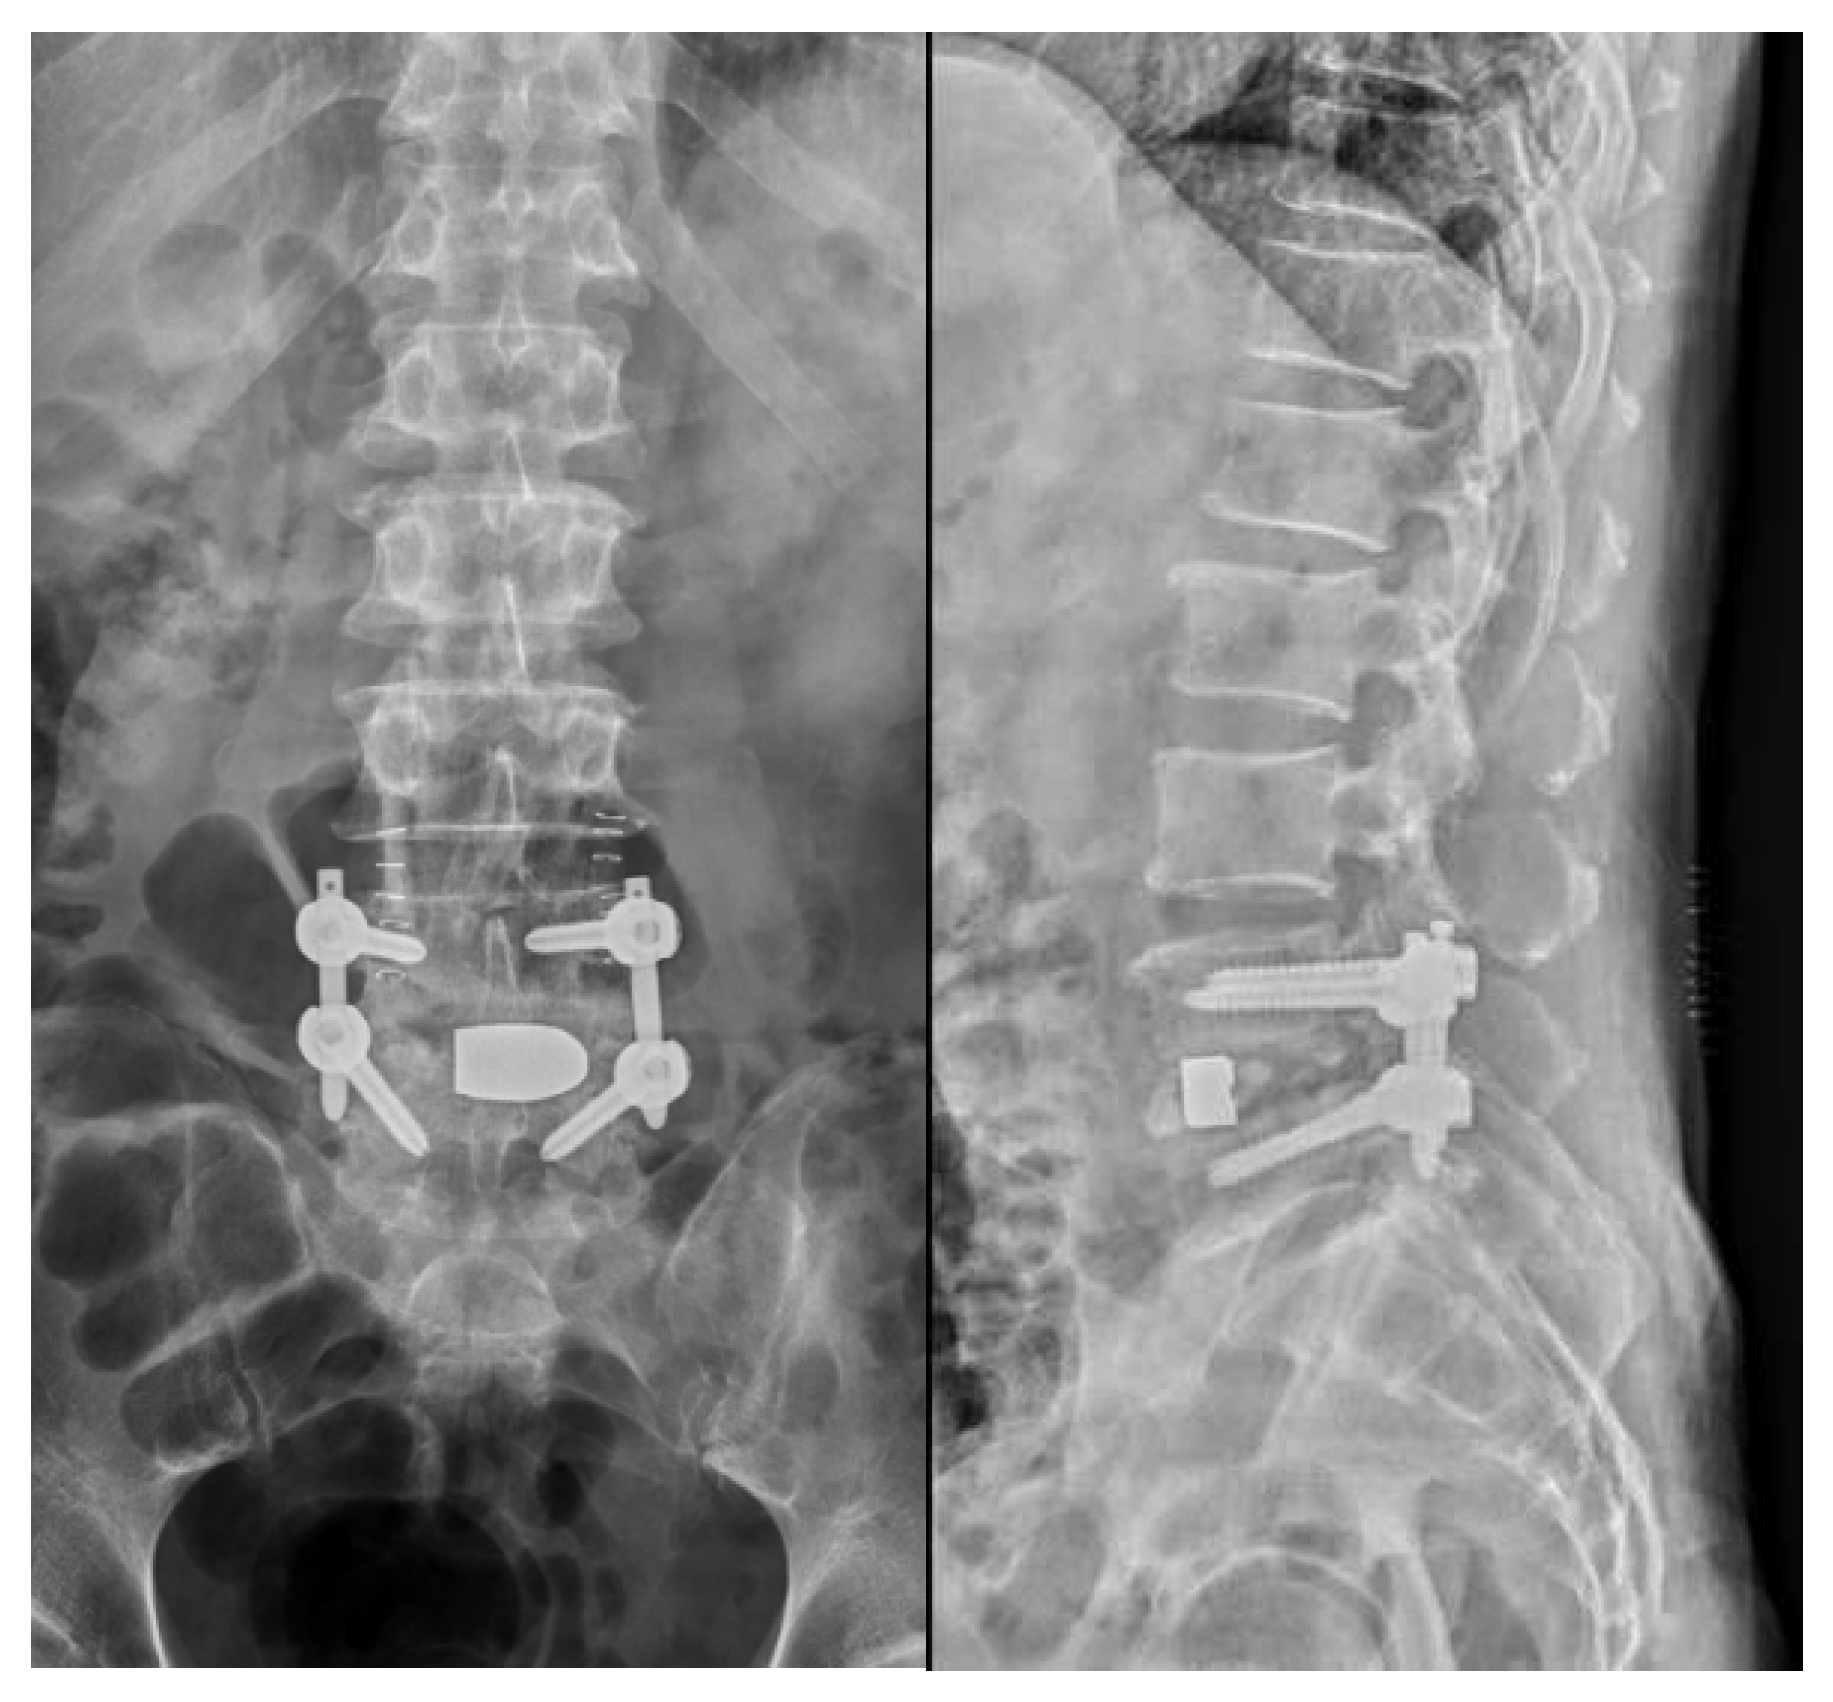

Figure 5. After minimally invasive transforaminal lumbar interbody fusion with TM cage and autologous & artificial bone grafts (L4/L5, via right side) and percutaneous posterior fixation with pedicle screws (L4 and L5, bilateral).